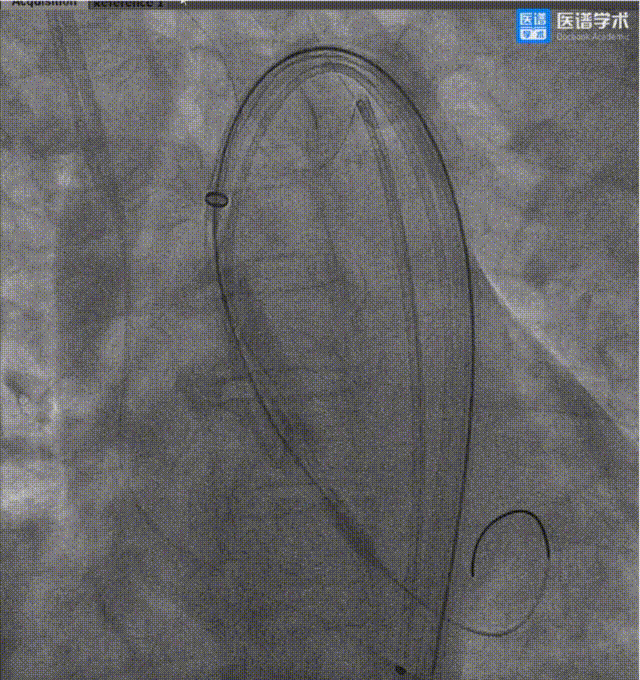

患者为66岁女性,三叶式主动脉瓣,瓣叶重度钙化(HU545:1155 mm³),术前经胸超声提示主动脉瓣口面积:0.56 cm²,平均跨瓣压差:42 mmHg,主动脉瓣口峰值流速:4.33 m/s,左冠开口低且瓣叶冗长,瓦氏窦、STJ、升主内径较小,若行TAVR存在极高的左冠开口堵塞与冠脉延迟闭塞风险,经心脏团队评估并结合患者意愿,最终决定采用TaurusWave冲击波技术进行治疗。经TaurusWave冲击波瓣膜治疗系统进行治疗,术中无起搏,术后脑保护装置未见血栓,即刻跨瓣压差下降50%,峰值流速下降20%,瓣口面积增加40%。

TaurusWave系统通过其特殊设计的球囊进行定位,在球囊扩张时,可以实现精准定向的脉冲式冲击波释放,达到安全、高效地松软破坏浅层与深层病灶钙化的效果。半顺应性囊体,针对三叶瓣和二叶瓣的特殊1D、3D型号与多尺寸设计,使TaurusWave系统可以适应更广泛的瓣膜解剖结构并更有效地传递冲击波能量至钙化病灶,从而提升瓣叶活动性,改善血流动力学。